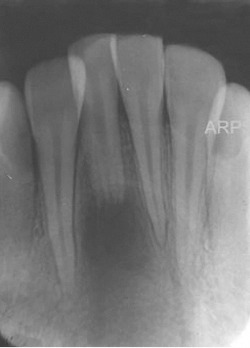

Fractura Radicular Vertical

Una fractura radicular vertical es una fisura que se extiende a lo largo de la raíz del diente, a menudo causada por un trauma o una presión excesiva.

Los pacientes suelen sentir dolor al morder y pueden notar hinchazón.

La fractura generalmente requiere la extracción del diente, ya que es difícil de reparar. Es crucial tratarla rápidamente para evitar infecciones.

Perforación Radicular

Una perforación radicular es una abertura anormal en la raíz del diente, generalmente debido a un procedimiento dental fallido o una caries profunda.

Los pacientes pueden sentir dolor y notar hinchazón en la encía.

El tratamiento incluye la reparación de la perforación y el tratamiento de conducto. Es crucial reparar la perforación para evitar una infección.